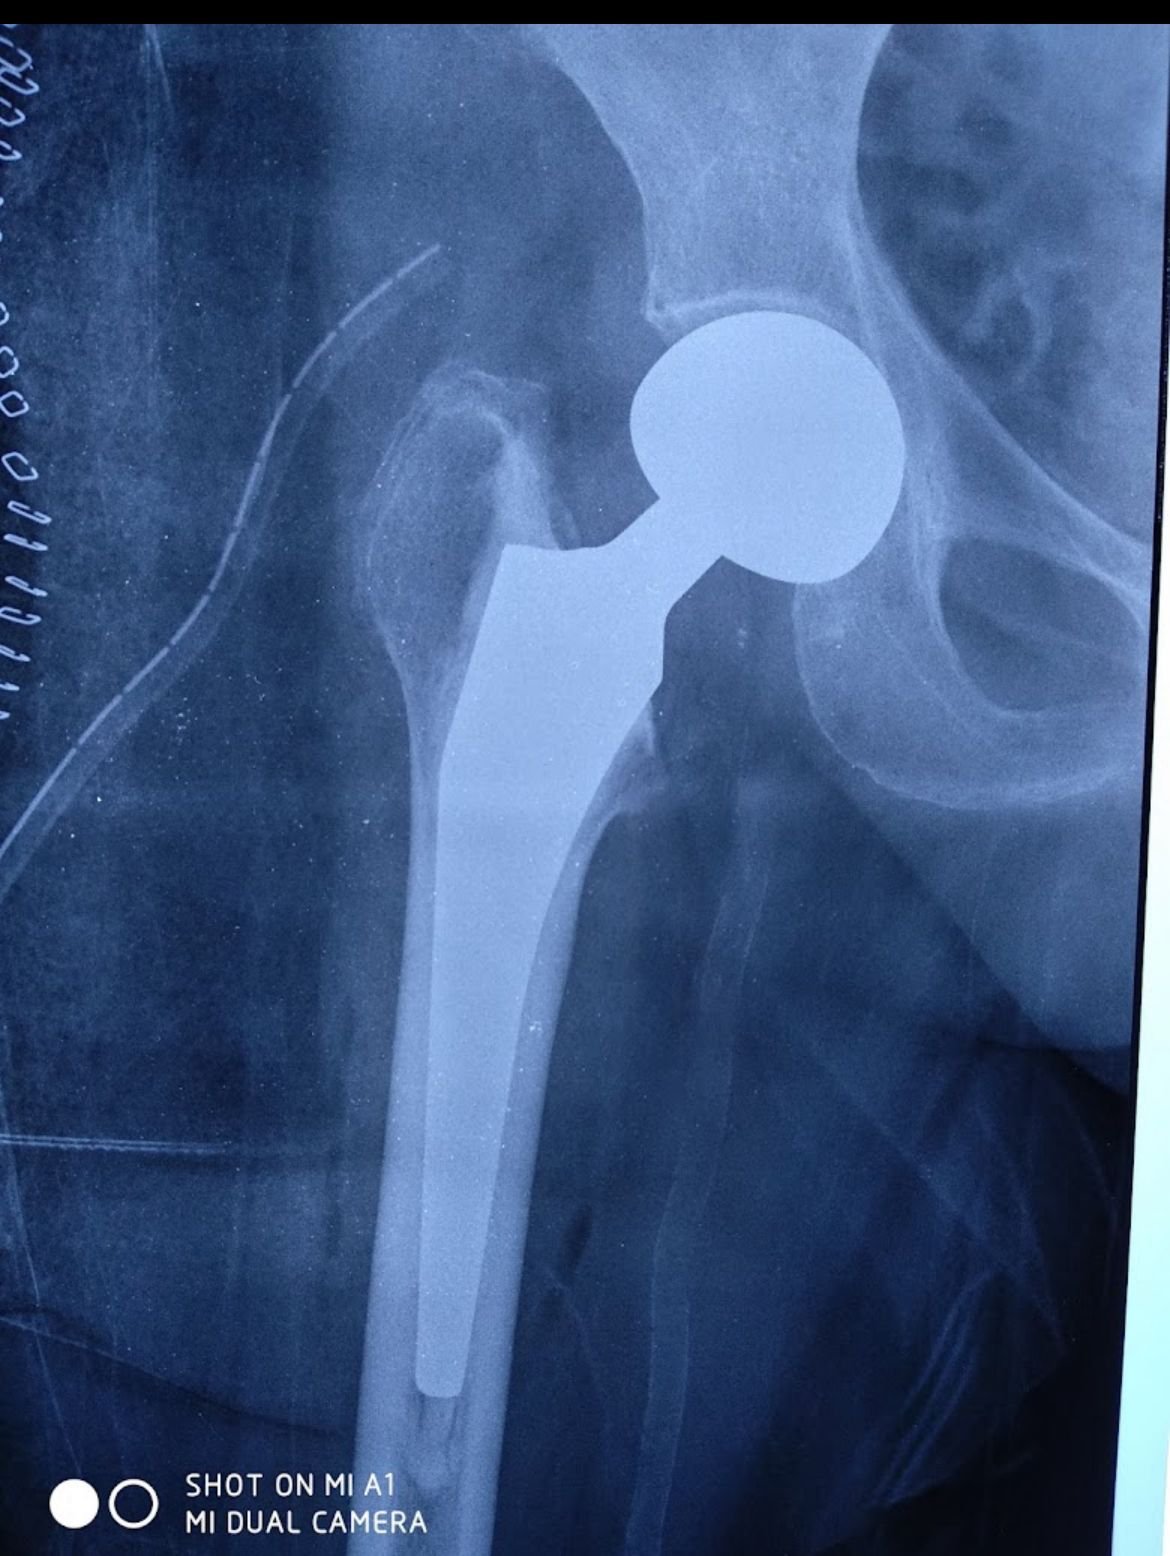

Hip Replacement

Gallery